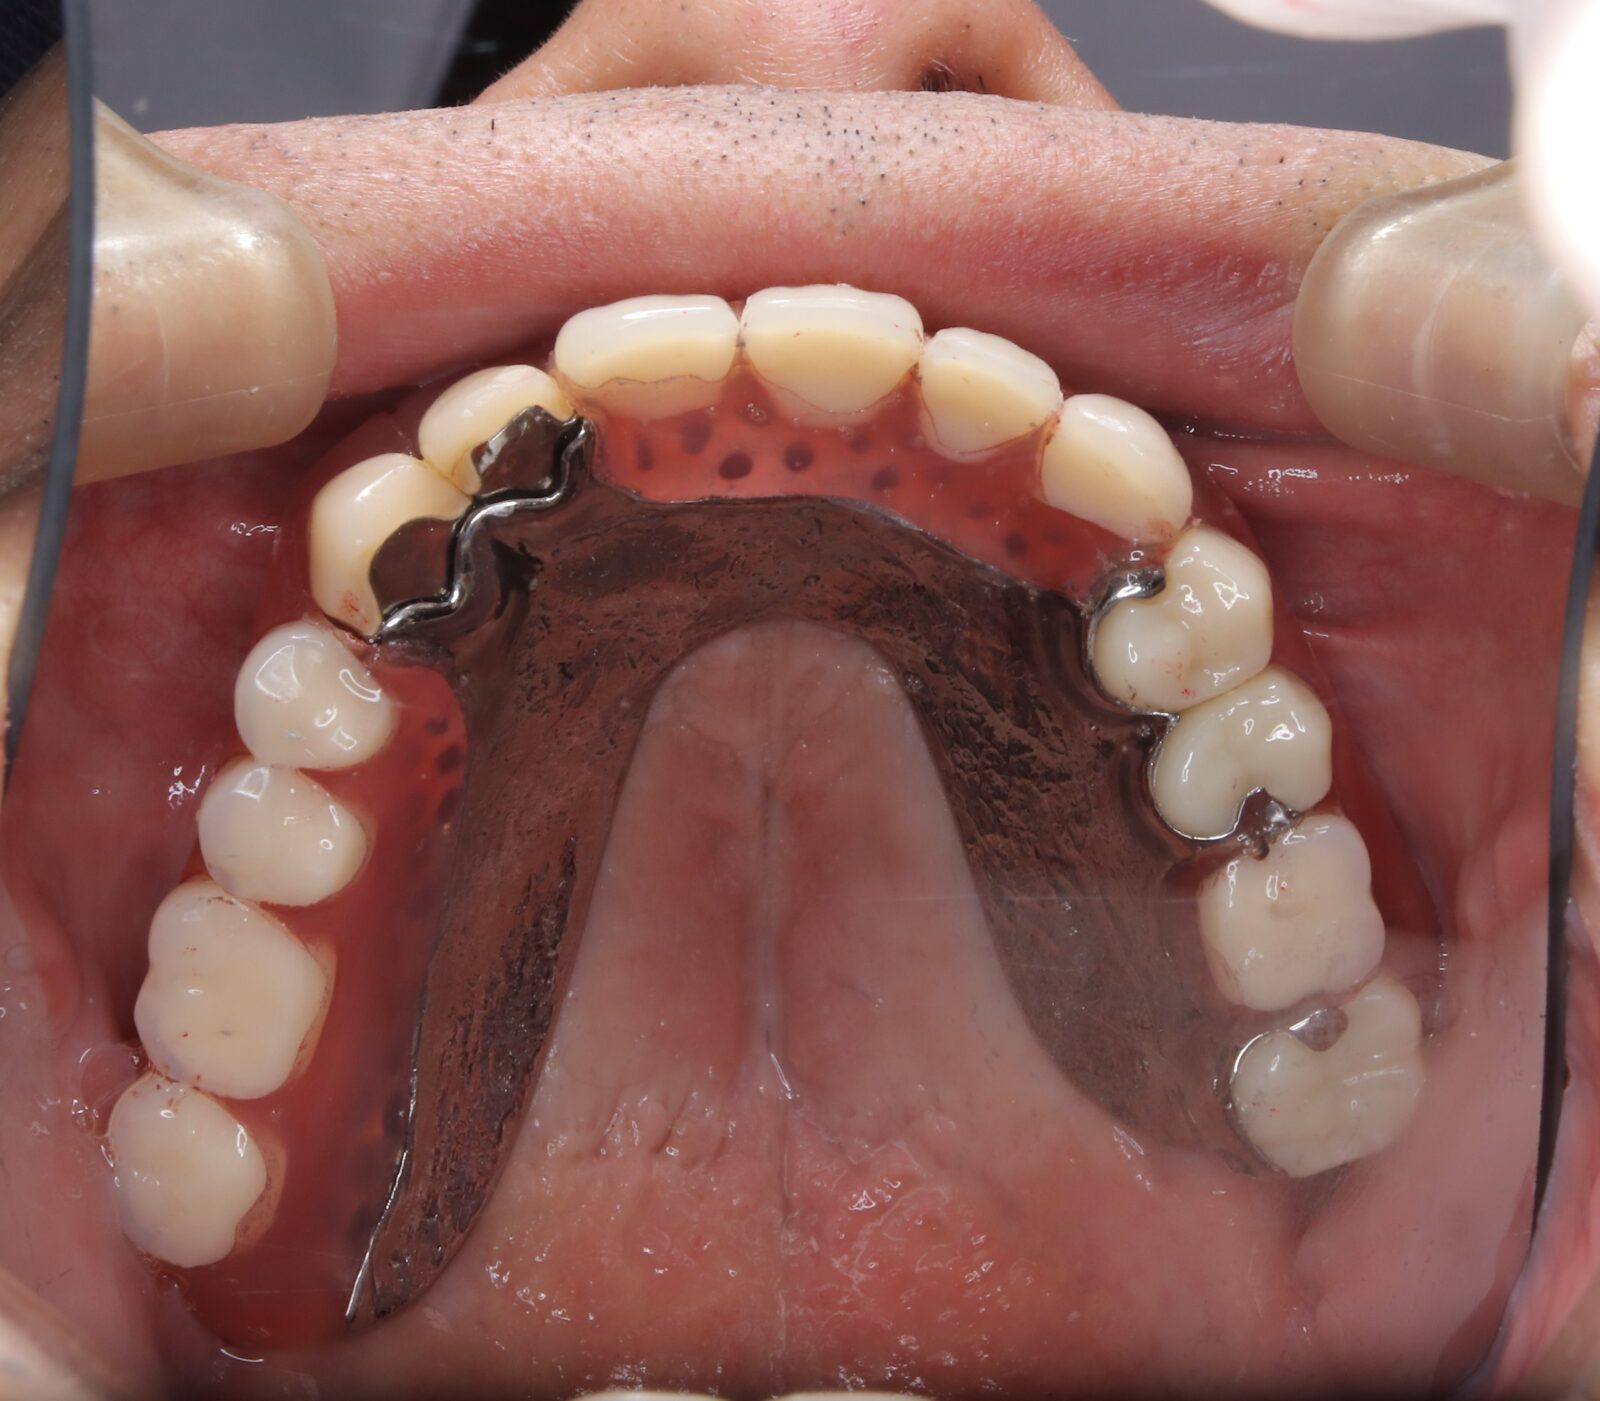

デンチャー+補綴+マウスピース矯正の症例

左上4〜7番に虫歯。右の親知らずの歯周ポケットは10mmあったため抜歯した。

左上6番の遠心は虫歯の範囲が大きすぎたため抜歯。義歯の安定を考慮すると、左上臼歯部をブリッジにするよりも、両側に義歯の人工歯を配置する方が良いと判断した。

本人の希望で薄く、口蓋を覆わない設計とした。

下顎前歯は抜歯後の治癒待ち、左上の虫歯治療中にインビザラインで歯列を整えた。

義歯作成期間中も歯の移動を行い、最終的には、計画通りに上顎の新義歯装着と同時に下顎のリテーナーを装着できた。

スマイルデンチャー

ジルコニアクラウン

インビザライン

治療期間約5ヶ月